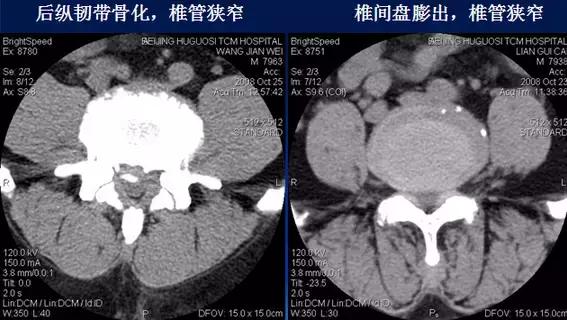

三、椎管狭窄

影像诊断标准:

①腰椎骨性椎管前后径≤15 mm示相对狭窄;≤12 mm绝对狭窄。

②硬膜囊前后径≤7 mm。

③椎间盘膨出、突出,侧隐窝狭窄(≤ 2mm),黄韧带肥厚(>5 mm),后纵韧带骨化,椎体后缘骨质增生等也可造成椎管有效面积狭窄。